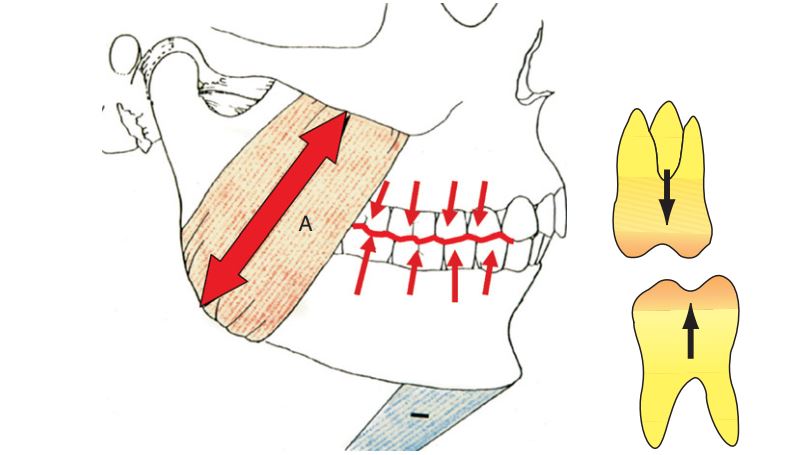

Kích thước dọc xảy ra khi răng ở trạng thái lồng múi tối đa (LMTĐ), nhưng răng không phải là yếu tố quyết định kích thước dọc mà chính chiều dài co cơ lặp đi lặp lại mới là yếu tố quan trọng xác định tương quan hai hàm, tạo nên kích thước dọc.

Kích thước (chiều dài) của các cơ nâng hàm khi co quyết định kích thước dọc cắn khớp.

Kích thước dọc cắn khớp (VDO) nói đến tương quan hàm dưới so với hàm trên theo chiều dọc khi các răng hàm dưới và răng hàm trên ở tư thế lồng múi. Mặc dù VDO xảy ra khi có đầy đủ răng trên cung hàm nhưng răng không phải là yếu tố quyết định của VDO. Hay nói rõ hơn, vị trí răng được quyết định bởi kích thước khoảng hở giữa hàm trên (cố định) với hàm dưới (được định vị bởi cơ).

Điều quan trọng cần biết về kích thước dọc là hàm dưới được hệ thống cơ nâng hàm hướng dẫn đến một vị trí và vị trí này có thể lặp lại được.

Điểm cân bằng đó (neutral point) chính là vị trí tối ưu cho hệ thống cơ co theo chu trình lặp đi lặp lại. Nếu không có răng đối thì cơ có thể co nhiều hơn, tuy nhiên sự đóng hàm theo thói quen là gần như không thể thay đổi, và nó là yếu tố quyết định KTD.

Trên thực tế, kích thước của tương quan hàm – hàm này luôn ổn định, đến mức những thói quen xấu như nghiến răng trầm trọng hay cắn chặt răng cũng không thể làm thay đổi nó.